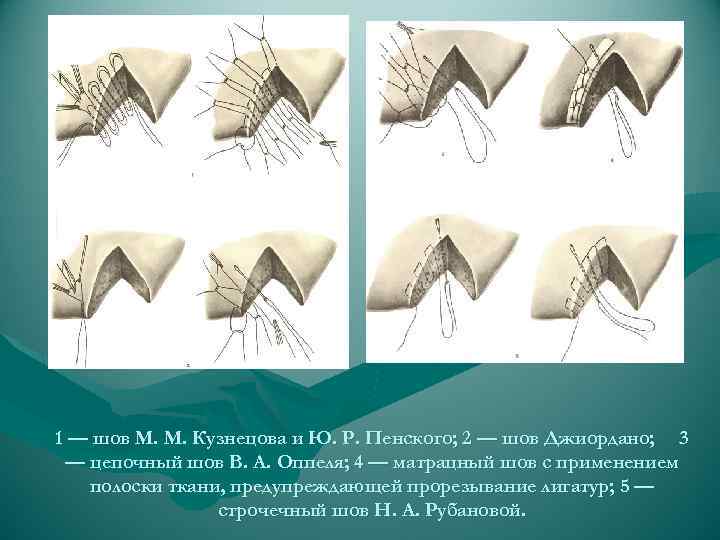

ХИРУРГИЧЕСКАЯ ТАКТИКА ПРИ РАНЕНИЯХ ПЕЧЕНИ Окончательная (обработка раны) - Тампонада раны марлей; - Биологическая тампонада - серповидной и круглой связками - мышцей - сальником - изолированный участок - лоскут на питающей ножке с фиксацией его к краям раны кетгутовыми швами (предпочтительнее) - Шов печени - сдавление краев кровотачащей раны с предварительным лигированием крупных сосудов; - шов Кузнецова-Пенского - матрацные швы - Дополнительная герметизация раны сальником, связкой, клеем - Резекция печени

ХИРУРГИЧЕСКАЯ ТАКТИКА ПРИ РАНЕНИЯХ ПЕЧЕНИ Окончательная (обработка раны) - Тампонада раны марлей; - Биологическая тампонада - серповидной и круглой связками - мышцей - сальником - изолированный участок - лоскут на питающей ножке с фиксацией его к краям раны кетгутовыми швами (предпочтительнее) - Шов печени - сдавление краев кровотачащей раны с предварительным лигированием крупных сосудов; - шов Кузнецова-Пенского - матрацные швы - Дополнительная герметизация раны сальником, связкой, клеем - Резекция печени

1 — шов М. М. Кузнецова и Ю. Р. Пенского; 2 — шов Джиордано; 3 — цепочный шов В. А. Оппеля; 4 — матрацный шов с применением полоски ткани, предупреждающей прорезывание лигатур; 5 — строчечный шов Н. А. Рубановой.

1 — шов М. М. Кузнецова и Ю. Р. Пенского; 2 — шов Джиордано; 3 — цепочный шов В. А. Оппеля; 4 — матрацный шов с применением полоски ткани, предупреждающей прорезывание лигатур; 5 — строчечный шов Н. А. Рубановой.